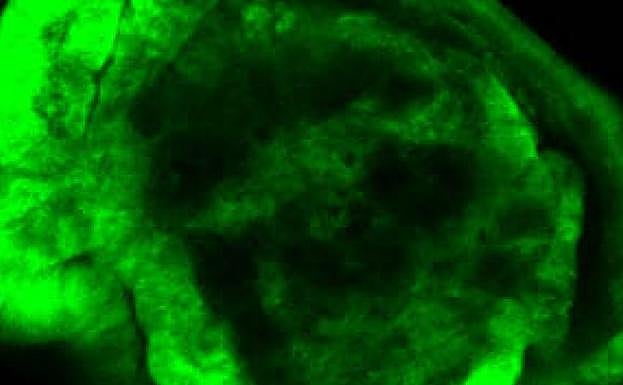

La sobre-expresión del gen Serpent en el ala de Drosophila provoca un sobrecrecimiento permanente y es suficiente para inducir tumores. Kyra Campbell, IRB

El equipo de Casanova estudió varios genes, entre ellos el gen Serpent (homólogo de GATA en Drosophila) y demostró que la sobreexpresión de este gen es suficiente para iniciar tumores ya que por sí solo promovía un sobrecrecimiento del tamaño del ala de la mosca, modificaba la estructura del tejido y activaba una serie de cambios genéticos para que se originara un tumor.